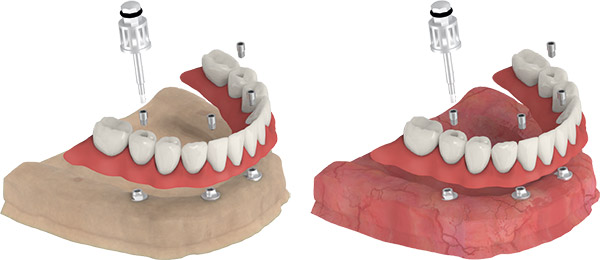

IMMEDIATE RESTORATION

- Manually mount and screw the temporary abutments onto the Multi-Unit and Multi-Base Abutments.

- Perforate the denture and prepare it to fit the temporary abutments so that the prosthesis does not put pressure on the mucosa.

- Manually assemble the healing caps by applying a slight torque (5-10 Ncm) by finger power.